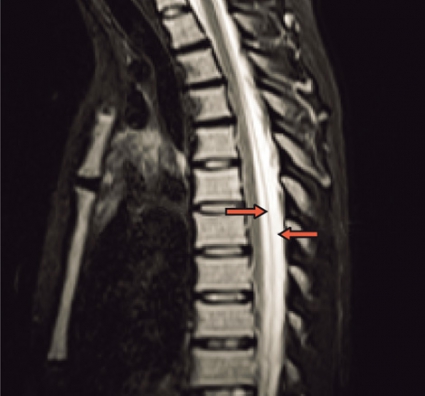

Spontan intrakraniell hypotension är sannolikt ett underdiagnostiserat tillstånd som man bör tänka på hos patienter med nytillkommen daglig huvudvärk, särskilt om den förvärras i stående (Fakta 1). För att ställa diagnos gäller att likvortrycket ska vara lågt, helst <6 cm H2O i liggande, och MRT med kontrast (helst före lumbalpunktion) ska visa generell dural uppladdning (s k pakymeningit) och karakteristiska förändringar av hjärnstammen (Fakta 2) [1, 2]. Initial behandling är symtomlindring med sängläge och gradvis mobilisering. Den kompletteras ofta med rikligt vätskeintag och koffein, antingen i tablettform eller som dropp. Om detta inte ger effekt är epidural injektion av autologt blod (»blood patch«) nästa steg, som ger snabb effekt hos de flesta patienter men som kan behöva upprepas [3]. Vid terapiresistens övervägs utvidgad neuroradiologisk utredning för att lokalisera likvorläckagestället. Då finns möjlighet att upprepa blodinjektionen över själva läckagestället. Om det inte hjälper kan kirurgiskt ingrepp diskuteras [2]. Etiologi och patogenes År 1938 beskrev den tyske läkaren Georg Schaltenbrand det tillstånd som kom att kallas spontan intrakraniell hypotension [4, 5]. Då trodde man att orsaken var minskad produktion av likvor från plexus choroideus eller ökad absorption, men bevis saknades. I dag vet man att tillståndet beror på likvorläckage, sannolikt på grund av en defekt i dura mater. Vid utredning har man kunnat påvisa spinala epidurala cystor (divertiklar) som bedömts ha rupturerat spontant eller vid en plötslig tryckstegring i likvorrummet. Det är också känt att osteofyter och diskbråck kan orsaka läckage genom att erodera duran [6, 7]. I dessa fall kan operation bli nödvändig [8]. Vid kirurgi kan man se många olika durala avvikelser, såsom rifter och meningeala cystor [9-11]. Spontan intrakraniell hypotension uppkommer förmodligen i vissa fall av en kombination av lindrigt trauma och underliggande spinal patologi [2, 12]. Enligt litteraturen har upp till en tredjedel av patienterna en oupptäckt bindvävssjukdom. Många har morfologiska tecken på bindvävssjukdom, såsom lång och smal kroppsbyggnad, spindelfingrar och överrörlighet i lederna [13, 14]. I de flesta fall är dock bindvävssjukdomen ospecifik, och endast i ca 5 procent av fallen har en specifik diagnos kunnat ställas, såsom Marfans syndrom eller Ehlers–Danlos syndrom typ II [13, 15-17]. Familjär spontan intrakraniell hypotension har även beskrivits [18]. Det är viktigt att veta att ett normalt spinalt öppningstryck (7–20 cm H2O) inte utesluter diagnosen [12]. Hos en patient med normalt tryck är det symtomen och tecknen på MRT som ger diagnosen. Många menar att förlust av likvor är den verkliga orsaken till syndromet och att hypotensionen är en följd av hypovolemin [19]. Likvorhypovolemisyndrom (CSF hypovolemia syndrome) har därför föreslagits som ett nytt namn på tillståndet [19]. Läckagestället är nästan alltid beläget i cervikotorakala delen, ofta i cervikotorakala övergången [12]. I praktiken kan det vara svårt att fastställa ett exakt läckageställe. Ofta samlas vätska bakom durasäcken i höjd med kotkropparna C1–C2 [20]. Denna vätskeansamling är dock inte ett säkert tecken på läckage från detta område. Det kan vara en falsk lokalisation. Sannolikt kommer läckaget från en annan nivå, och vätskan förflyttas uppåt till övre halsryggen [20]. Ibland kan man se multipla läckageställen samtidigt [21]. Epidemiologi Spontan intrakraniell hypotension har länge ansetts vara mycket sällsynt. Men kanske är tillståndet inte så ovanligt. Inga säkra siffror från samhällsbaserade studier finns tillgängliga för att beräkna incidensen och prevalensen. I en studie av radiologiska undersökningar på en akutavdelning diagnostiserades sjukdomen ungefär hälften så ofta som spontan subaraknoidalblödning – med en uppskattad årlig incidens på 5/100 000 [22]. På ett sjukhus i Rom diagnostiserades 82 patienter under en 18-årsperiod, 1992–2009, av vilka 40 behandlades konservativt med sängläge och 42 med lumbal epidural injektion av autologt blod [3]. På vår klinik har vi haft 10–15 patienter med detta tillstånd de senaste fyra åren. Den högsta incidensen av spontan intrakraniell hyptension ses vid vid ca 40 års ålder, men fall har beskrivits hos personer mellan 3 och 86 års ålder. Sjukdomen tenderar att drabba kvinnor något oftare än män (kvot ca 1,5:1) [2]. Kliniska symtom Den vanligaste kliniska manifestationen av spontan intrakraniell hypotension är ortostatisk huvudvärk, som förvärras gradvis med maximal intensitet efter flera minuter till timmar. Det händer att huvudvärken debuterar plötsligt. Man misstänker då ofta subaraknoidalblödning, och patienten utreds av denna anledning [23]. De allra flesta patienter kan minnas dagen då huvudvärken började, om än inte den exakta tidpunkten. Huvudvärken brukar beskrivas som diffus, pulserande eller icke-pulserande och är vanligen lokaliserad till nackregionen men kan också vara frontotemporal. Huvudvärken behöver inte vara symmetrisk men är sällan helt ensidig. Hur allvarlig huvudvärken är varierar, och det är troligt att en del lindriga fall förblir oupptäckta och att läkning sker spontant. En ledtråd till diagnosen kan vara om patienten beskriver en dragningskänsla från huvudet ner till nacken. Ytterligare ledtrådar är om patienten föredrar att ligga ned på undersökningsbritsen eller har en kudde med sig [2]. Även om ortostatisk huvudvärk är det kliniska kännetecknet, vilket återspeglas i alla diagnostiska kriterier, är det välkänt att den ortostatiska komponenten ofta blir mindre framträdande eller försvinner med tiden. Dessutom har patienter vars huvudvärk från början har saknat ortostatisk komponent beskrivits [24, 25]. Den exakta orsaken till huvudvärken är inte känd, men man antar att det är förlusten av likvor som orsakar neddragningen av hjärnan med sekundär dragning av smärtkänsliga intrakraniella strukturer [12]. En alternativ förklaring är att det sker en kompensatorisk dilatation av smärtkänsliga intrakraniella venösa strukturer. Förutom huvudvärk har många andra symtom rapporterats. De vanligaste, som förekommer i mer än hälften av fallen, är nacksmärta eller nackstelhet, illamående och kräkningar. Upp till hälften av patienterna beskriver lockkänsla eller tinnitus, och ca 10 procent uppvisar kranialnervspåverkan (vanligtvis abducenspares) med dubbelseende [12]. Abducensnerven har en lång och komplicerad väg intrakraniellt och är därför särskilt utsatt. MRT-undersökning av hjärnan MRT har revolutionerat inte bara erkännandet av sjukdomen utan också förståelsen av den [2]. MRT har i hög grad underlättat möjligheten att komma fram till en säker diagnos utan att behöva använda ingrepp som lumbalpunktion. MRT är förmodligen den viktigaste faktorn bakom det ständigt ökade antalet patienter med spontan intrakraniell hypotension sedan början av 1990-talet [2]. Det typiska fyndet vid cerebral MRT är generell pakymeningit (Figur 1). Pakymeningit i samband med spontan intrakraniell hypotension beskrevs första gången år 1991 av Mokri et al [26]. Det är dock viktigt att veta att upp till 20 procent av patienterna med spontan intrakraniell hypotension inte har någon tydlig pakymeningit [27]. Man tror att den meningeala förtjockningen beror på dural vasodilatation. Grunden för detta är Monroe–Kellie-doktrinen, enligt vilken summan av intrakraniellt blod, likvor och hjärnvävnad ska vara konstant i ett intakt kranium. Det innebär att minskningen av likvor leder till kompensatorisk vasodilatation [12, 19]. De flesta av förändringarna som ses vid MRT kan förklaras av dessa kompensatoriska mekanismer med pakymeningeal uppladdning, vidgning av venösa strukturer och hypofysförstoring. »Sagging«, eller neddragning, av hjärnan är ett typiskt radiologiskt fynd vid spontan intrakraniell hypotension (Figur 2). Det ses tydligast på en sagittal MRT-bild med neddragning av hjärnstam och lillhjärnstonsiller genom foramen magnum som vid Chiari-missbildning typ 1 (Figur 2). Subdural vätska (effusioner och hematom) förekommer hos ca 50 procent av patienterna (Figur 3). Oftast är dessa vätskeansamlingar tunna, bilaterala och lokaliserade till ovanför storhjärnshemisfärerna, orsakade av bristningar i bryggvener, utan någon märkbar expansiv effekt. Vätskeansamling ses ibland i bakre skallgropen, särskilt över lillhjärnshemsifärerna eller bakom clivus. Dessa vätskeansamlingar brukar försvinna när behandling sätts in mot det underliggande spinala likvorläckaget 28]. Om kirurgin riktas endast mot vätskeansamlingarna utan att läckaget behandlas är risken för recidiv ganska stor. Hypofysär hyperemi med förstoring av körteln är ett annat radiologiskt tecken på spontan intrakraniell hypotension [29]. Förstoringen kan bli ganska anslående och kan likna en hypofystumör. Det finns många tillstånd som radiologiskt kan likna spontan intrakraniell hypotension. Den förtjockade kontrastladdade duran kan misstolkas som ett kroniskt subduralhematom, men i dessa fall ses i regel ett vätskespatium mellan uppladdningarna. Idiopatisk hypertrofisk pakymeningit ger oftare fokal, dural förtjockning och inte den jämna, kontinuerliga uppladdningen som vid hypotensionssyndromet. Framför allt gäller detta vid granulomatös meningit och meningeal karcinomatos, vilka också oftare drabbar de mjuka hinnorna än den hårda hjärnhinnan. Meningealt lymfom och durala metastaser liksom meningiom med »dural svans« har ofta associerade skelettförändringar. Vid alla ovan nämnda tillstånd saknas dessutom den typiska bilden av neddragen hjärna. Spinal MRT Spinal MRT kan visa områden med extradural vätskeansamling (särskilt vid C1–C2) (Figur 4 och 5), meningeala divertiklar, dilatation av epidurala vener, dural uppladdning och komprimerad durasäck [30-32]. DT-myelografi Lumbalpunktion med injektion av jodkontrast följt av DT-myelografi med tunna snitt och reformateringar av hela ryggraden har visat sig vara en bra metod för att definiera läckagets exakta lokalisering och omfattning. DT-myelografi har visat sig ha störst känslighet vad gäller att lokalisera läckagestället [32]. Icke-invasiva undersökningar som spinal MRT rekommenderas dock i första hand [33]. Myelografi med intratekal administration av gadolinium följt av MRT är ett alternativ som ibland används utomlands [34] men är ännu inte godkänd på indikationen spontan intrakraniell hypotension i Sverige. Lumbalpunktion Vanligtvis är öppningstrycket <6 cm H2O, och det kan vara omätbart. Det är dock väl dokumenterat att en del patienter med spinalt likvorläckage kan ha ett normalt öppningstryck [33]. Den förhöjda halten av protein och/eller förekomst av xantokromi beror troligen på ökad permeabilitet i dilaterade meningeala blodkärl. Behandling Även om detaljerade uppgifter saknas sker sannolikt spontanläkning i de flesta fall av spontan intrakraniell hypotension. Symtomlindring med sängläge och gradvis mobilisering är en väldokumenterad behandling [12]. Koffein och teofyllin har också visat viss effekt [12]. Om sängläge inte hjälper är den vanliga behandlingen injektion av autologt blod (10–30 ml) epiduralt i ländryggen [35]. Om behandlingen misslyckas kan den upprepas en till två gånger, och man kan då spruta in större mängder blod, upp till 40 ml. Med tanke på den potentiellt stora volymen blod som injiceras rekommenderas några dagars mellanrum vid upprepad behandling. Volymen blod som kan injiceras begränsas huvudsakligen av ryggsmärta eller radikulopati. Det rekommenderas att patienten bibehåller planläge efter injektionen för att minska likvorflödet genom duradefekten och därmed hjälpa till att stänga hålet. Det har diskuterats om injektion av autologt blod verkligen hjälper när läckagestället är på cervikotorakal nivå. En del rapporter finns som visar att behandlingen är effektiv [36, 37]. I den tidigare nämnda studien från Rom [3] behandlades 42 patienter med spontan intrakraniell hypotension på dettta sätt med stor framgång, trots att läckaget i de flesta fall var på cervikotorakal nivå. 38 patienter (90 procent) blev återställda efter ett ingrepp, 2 patienter (5 procent) efter två ingrepp och 2 patienter (5 procent) efter tre ingrepp. Författarna rekommenderar dock konservativ behandling under tio dagar innan blodinjektion ges. Romgruppen lät patienterna ligga i Trendelenburgläge 1 timme före och 24 timmar efter ingreppet. Intressant nog behandlade de patienterna med acetazolamid, 250 mg i tablettform, 18 och 6 timmar före ingreppet. Acetazolamid är en karbanhydrashämmare som minskar produktionen av likvor. Romgruppen för ett resonemang om huruvida premedicineringen och långvarigt Trendelenburgläge kan minska likvorflödet genom duradefekten och därmed hjälpa till att stänga hålet. Dessutom kan premedicineringen minska risken för återuppkomst av tillståndet [38]. Om den lumbala blodinjektionen inte hjälper kan man försöka injicera blod eller fibrinlim (Tissel) direkt över läckagestället. Dessa behandlingar kräver att läckagestället är känt. Placering av fibrinlim ger förmodligen den bästa symtomlindrande effekten [39]. När konservativ behandling och blod eller fibrinlim inte ger effekt kan kirurgi vara ett alternativ [8, 12]. Kirurgi innebär bl a ligering av meningeala divertiklar, packning med spongostan, fibrinlim eller gelskum i epidurala rummet, suturering av durarifter samt resektion av osteofyter och diskbråck. Prognos Långtidsuppföljningarna av naturalförlopp och behandlingsresultat är knapphändiga, men spontan intrakraniell hypotension tros återkomma hos ca 10 procent, oavsett behandling. Patienter med en radiologisk bild som är typisk för spontan intrakraniell hypotension och med känt läckageställe har utmärkt prognos, medan personer med normal MRT-undersökning och diffus spinalt likvorläckage på flera nivåer tycks ha sämre prognos [2]. Vissa patienter har kvarstående symtom efter behandling trots dokumenterat upphävt likvorläckage. Dessa patienter är svåra att behandla, och det är oklart om de har förändrad likvordynamik eller kanske små rester av likvorläckage som inte syns på röntgenbilder. * Potentiella bindningar eller jävsförhållanden: Inga uppgivna.